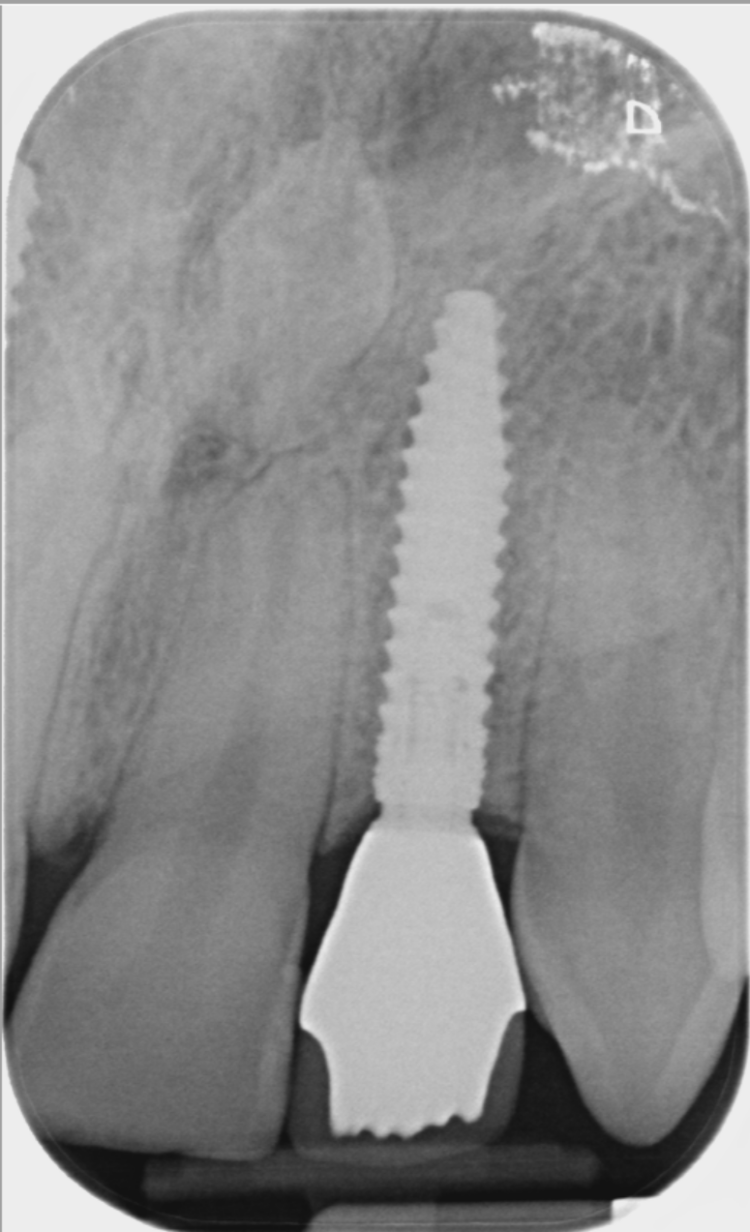

On the day of surgery, a split-thickness envelope flap was raised. Two CONELOG® Progressive-Line implants were placed through the surgical guide in the pre-determined lateral incisor positions. Soft tissue augmentation was performed simultaneously with the implant placement, and the site was sutured and closed without tension. The implants were immediately loaded using provisional crowns that were pre-fabricated in the lab.

The CONELOG implants were selected because they provide a very stable connection and feature a geometry that facilitates high primary stability, which is important when placing immediate implants. They also integrate very successfully – we have had better results with these implants than with other products that are available. I also appreciate the simplicity of the keyless guided surgery kit.